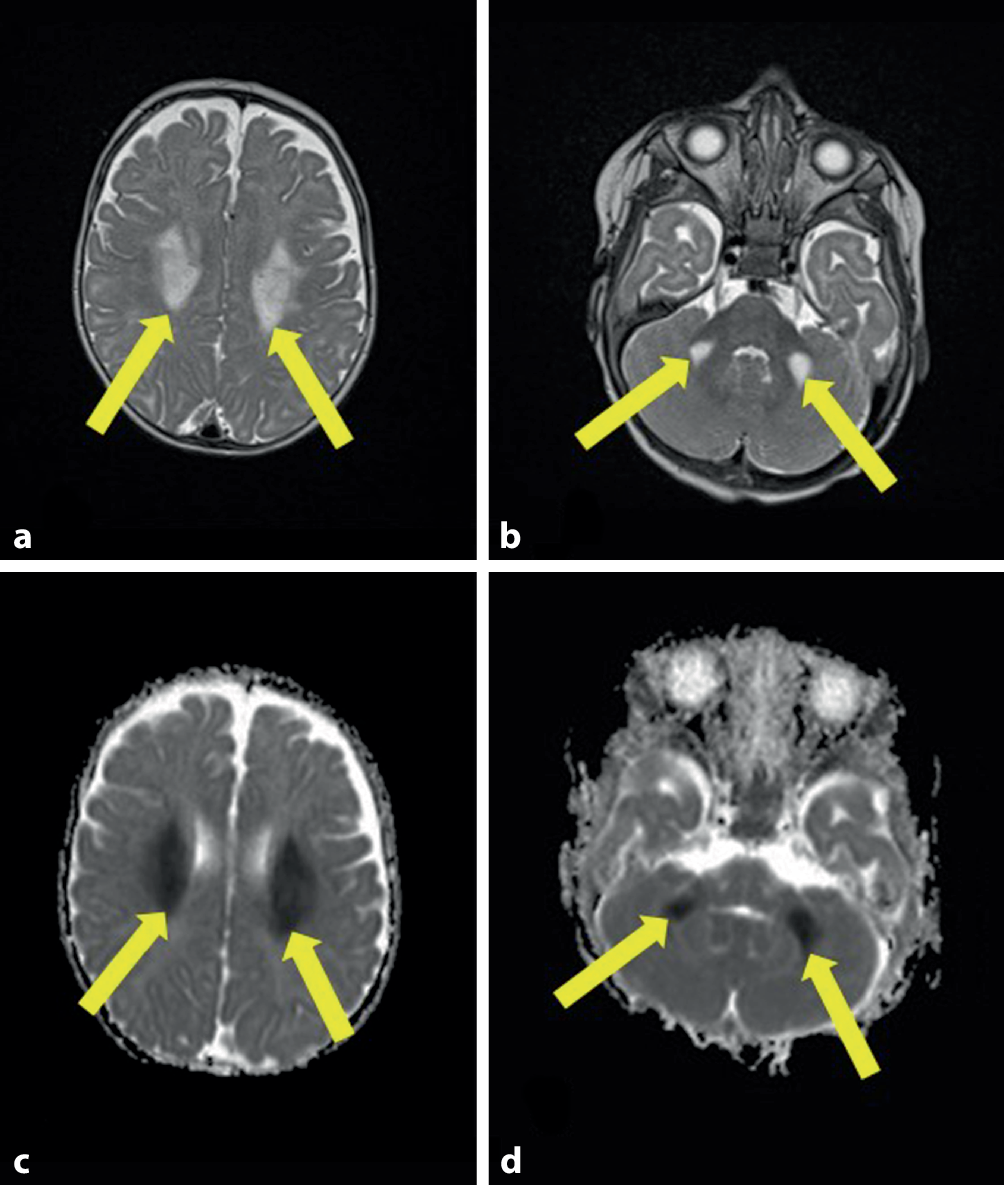

Abb. 2 (ursprüngliche Fassung)

Zerebrales MRT (axiale T2w, axiale „ADC maps“) bei dem Patienten im Alter von 6 Monaten: a bilaterale symmetrische Signalalterationen der weißen Substanz im Bereich der Corona radiata (aPfeile) und an der Basis des mittleren Kleinhirnstiels (bPfeile). cd Die Signalalterationen weisen eine Diffusionsrestriktion auf (Pfeile)

Bild vergrößern